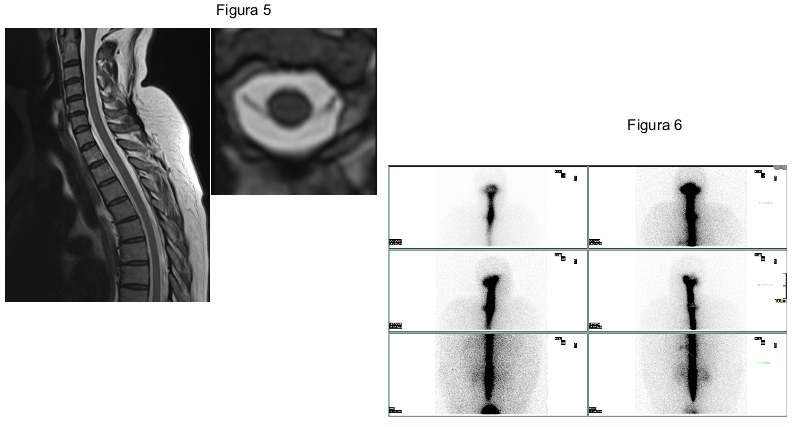

FIGURA 5. RM sagital y axial T1: Colección espinal extradural longitudinal anterior que se extiende de C7 a D4, contenido de intensidad de señal líquido, levemente superior a la señal del líquido intradural, sin deformidad ni alteración de señal de la médula.

FIGURA 6- Cisternografía: extravasación patológica del radiotrazador a la altura aproximada de D4, en el lado derecho, y de D9 en el izquierdo.